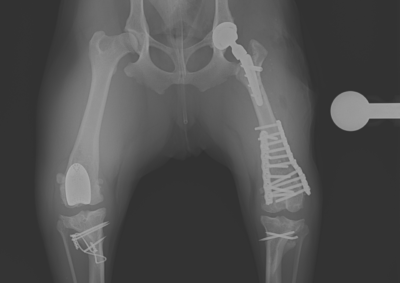

注意 ボタンをクリックした先に、治療中および手術中の画像が説明で使用されている場合がございます。 そのような画像に弱い方は閲覧なさらないようお願いいたします。 整形外科 若齢犬の橈骨固定術 #271 整形外科 前十字靭帯断裂(中型犬)に対するCBLO #255 整形外科 超小型犬に対する上腕骨遠位Y字骨折 整形外科 大型犬の前十字靭帯疾患(慢性経過)に対するCBLO #254 整形外科 橈骨固定術 #270 整形外科 膝蓋骨内方脱臼に対する人工滑車置換術 PGR #23 整形外科 犬の前十字靭帯(疾患)部分断裂に対するCBLO #253 整形外科 犬の前十字靭帯断裂に対するCBLO #252 整形外科 膝蓋骨内方脱臼+前十字靭帯断裂に対するPGR#22・LSS 整形外科 大腿骨骨折 整形外科 橈骨固定術 #269 整形外科 上腕骨外顆骨折の癒合不全 123456> 症例カテゴリー 放射線治療整形外科軟部組織外科脳神経外科内科腫瘍外科救急・集中治療リハビリテーション科腫瘍内科内視鏡科脳神経科呼吸器外科中医・漢方猫の腎移植循環器科